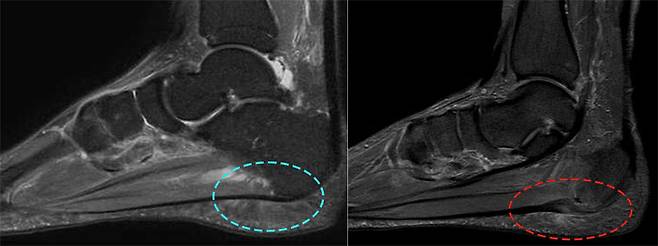

<정상 족저근막(좌) 및 손상되어 두꺼워진 족저근막(우) 자료제공:의정부 연세베스트병원 장철영 병원장> 날이 추워지는 겨울철에는 낮아진 기온으로 인해 발바닥 근육과 인대가 쉽게 굳어져 족저근막염 발병률이 높아진다. 정상>

초기 치료로는 발바닥의 피로를 줄이는 뒤꿈치 패드나 맞춤 깔창 등의 보조기구들과 함께 진통소염제, 체외충격파 치료 등 보존적 치료를 시행한다. 간혹 스테로이드 주사를 사용하기도 하는데, 반복된 스테로이드 주사는 오히려 퇴행성 변화를 가속화시키므로 주의가 필요하다. 6개월 이상의 보존적 치료에도 효과가 없거나, 초음파 또는 MRI 검사에서 근막의 두께가 4mm 이상 두꺼워진 경우에는 수술적 치료를 고려해야 한다.